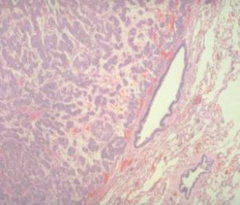

Caseating granuloma

-caseous necrosis in the center of the granuloma (one side of Slide). -Zones of epithelioid histiocytes and lymphocytes at the other side surround the caseous material.